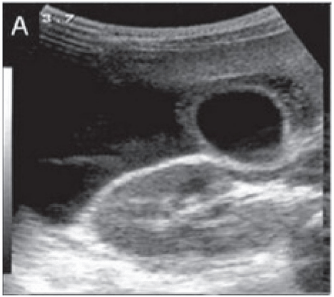

A febre do dengue hemorrágico (FDH) é uma arbovirose responsável por epidemias anuais no Brasil. Sua principal característica é o aumento da permeabilidade capilar, representada pela fuga de líquido e albumina para o espaço extravascular, levando a derrames cavitários e hemoconcentração com elevação do hematócrito, descrita como polisserosite, classificada em formas leves e graves, segundo critérios da Organização Mundial da Saúde. Embora os achados à ultrassonografia sejam inespecíficos, o método contribui para o diagnóstico precoce em pacientes com FHD e no diagnóstico diferencial de outras doenças febris.

Considerando as informações abaixo, assinale a alternativa correta quanto a principal hipótese diagnóstica da imagem ultrassonográfica apresentada.

Considerando as informações abaixo, assinale a alternativa correta quanto à principal hipótese diagnóstica da imagem ultrassonográfica apresentada.